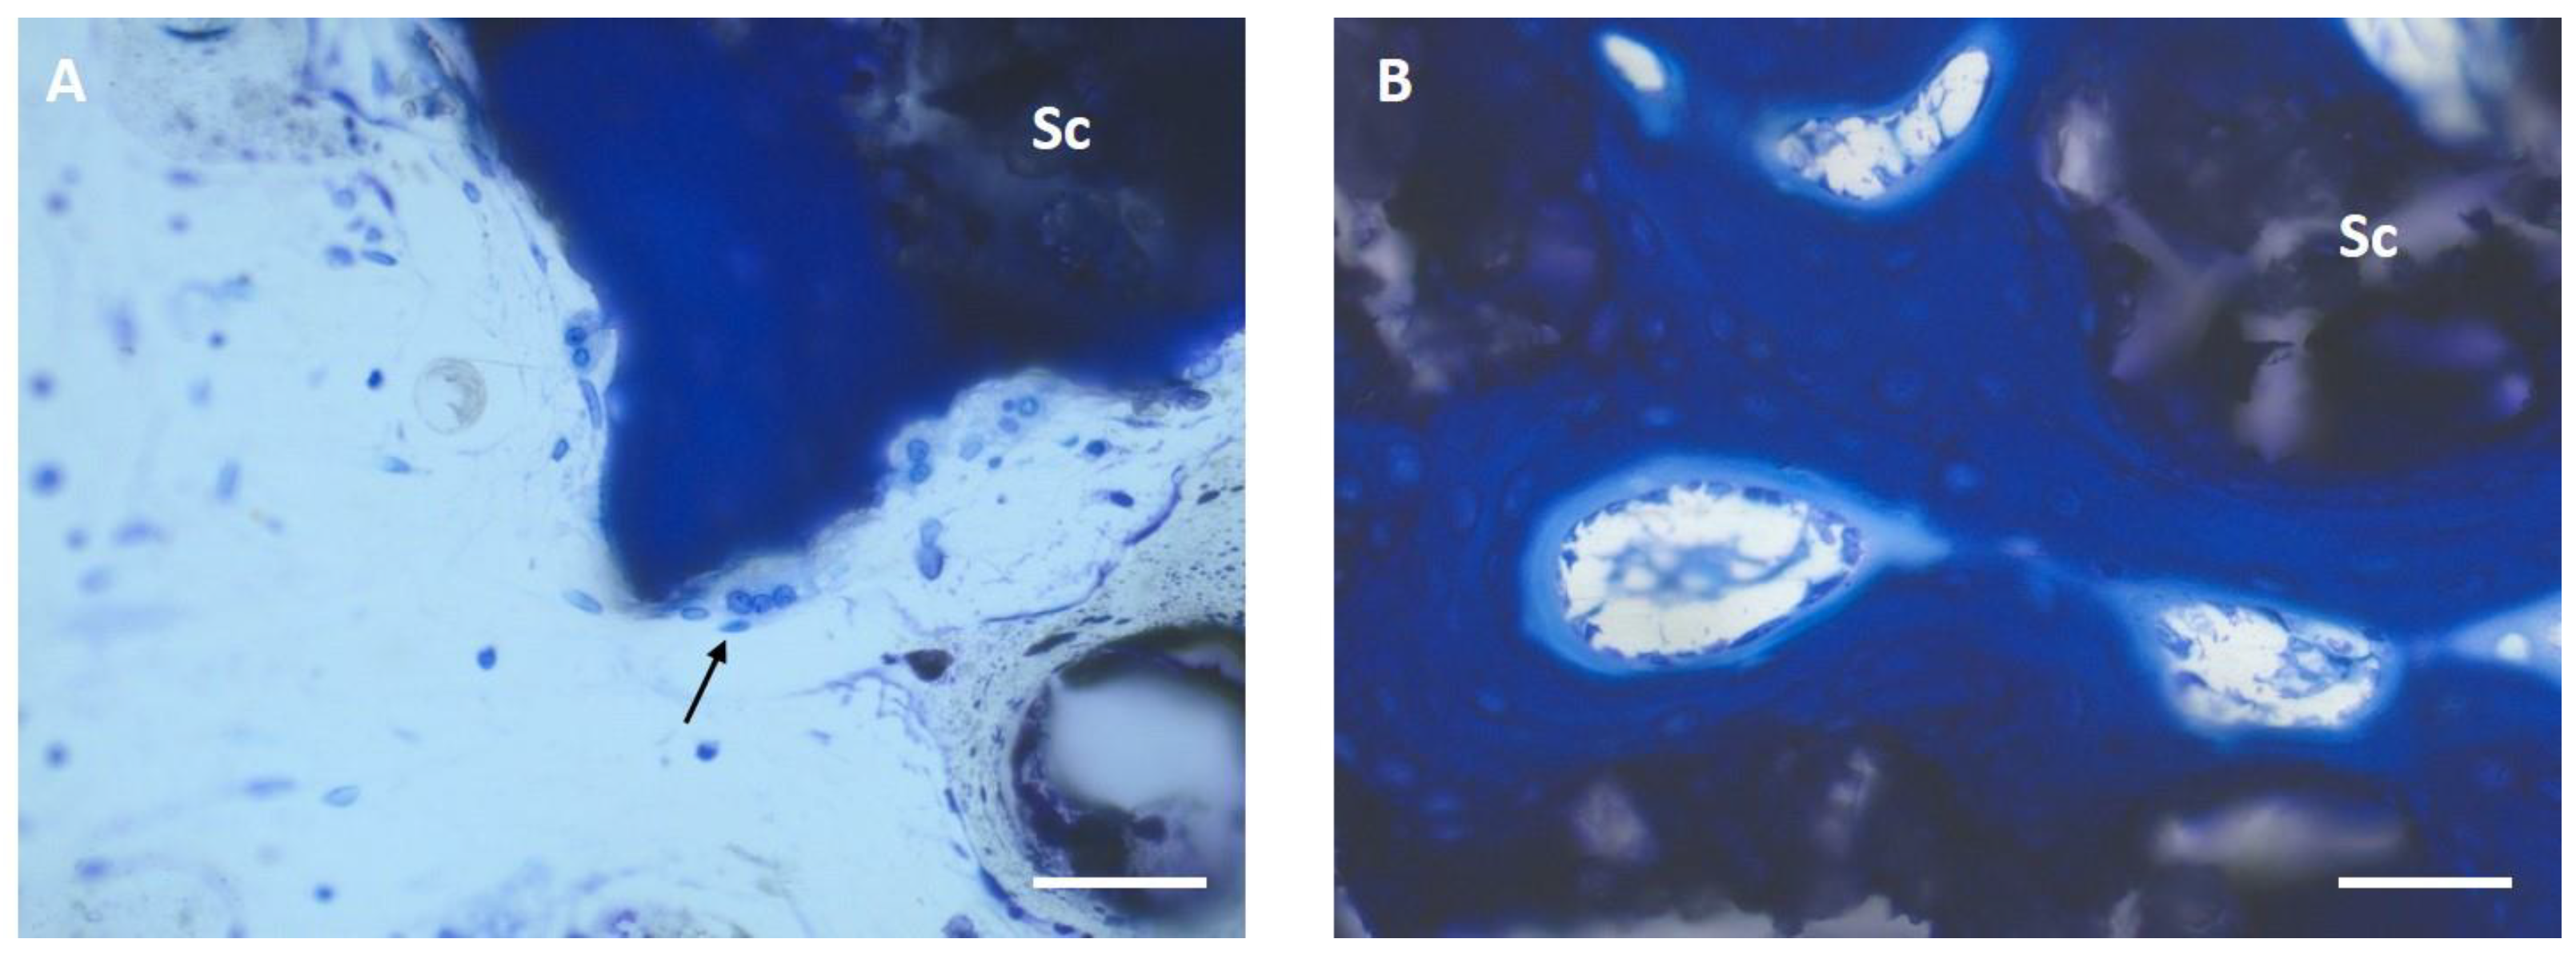

3.6. Histological Examination

3.6.1. Semi-Quantitative Assessment

3.6.2. Histomorphometric Examinations